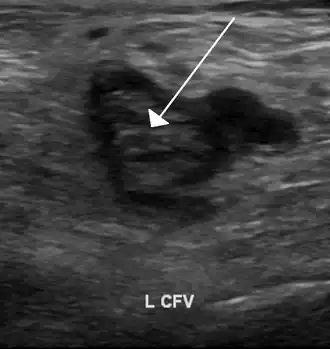

An abdominal CT scan demonstrating an iliofemoral DVT, with the clot in the right common iliac vein of the pelvis